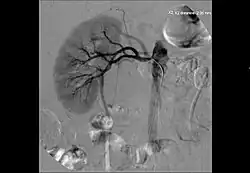

Las técnicas de diagnóstico por imagen utilizadas preferentemente son la ecografía doppler, la tomografía computerizada y la resonancia magnética. La Arteriografía por Sustracción Digital (ASD) es la exploración diagnóstica que confirma la estenosis o obstrucción, y es el paso previo al tratamiento endovascular percutáneo.

El tratamiento tiene el objetivo de recuperar el calibre de la arteria renal, mediante diferentes técnicas de revascularización. Estas pueden ser percutáneas o quirúrgicas. En la estenosis de la arteria renal, la primera opción de tratamiento es la revascularización por vía percutánea.